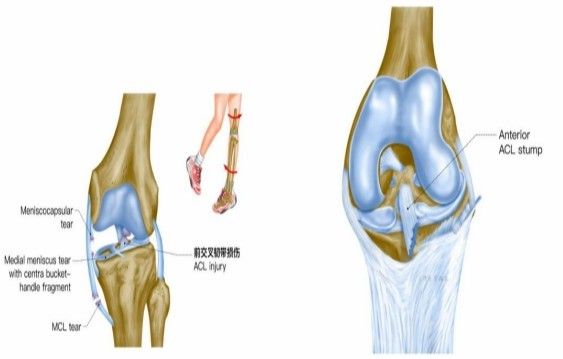

我院骨科三病區近期收治了4名膝關節交叉韌帶損傷患者。25歲的齊先生,因打籃球時不慎扭傷左膝,致右膝腫痛,遂來我院治療;30歲趙先生酷愛足球,扭傷右膝關節來我院就診;50歲的張先生、42歲劉先生因騎車滑倒摔傷、膝關節腫痛不適、活動受限,收治入院。骨科三病區李鵬主任團隊詳細查體以及完善影像學檢查后進行診斷:幾位患者共同診斷均有“前交叉韌帶損傷”,不同程度合并有“半月板損傷”、“股骨軟骨損傷”、“內側副韌帶斷裂”。

致傷機制

單純前交叉韌帶損傷可發生于非負重條件下膝強力過伸時(如用力踢時未遇到抵抗),或小腿固定、暴力使股骨向后時。單純前交叉韌帶損傷少見,多合并脛側副韌帶、半月板的損傷,此三結構的復合傷在膝部韌帶損傷中最為常見(占52%)。損傷多發生于韌帶中部(占 72%),少數發生于股骨附著點撕脫骨折 (18%)或脛骨附著點撕脫骨折(4%)。損傷后關節內出血、疼痛、活動受限、前抽屜試驗陽性。